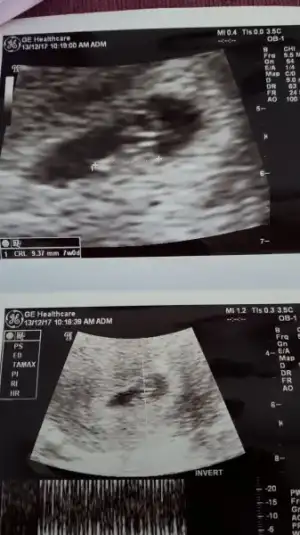

Kızlar bizde 7+2haftalıgız cinsiyetimiz ne olabilir acaba?cok merak ediyorum

Eklentiler

• F2E71B90-F47B-4C81-8FF7-DB126662D2B2.webp

F2E71B90-F47B-4C81-8FF7-DB126662D2B2.webp

6,4 KB · Görüntüleme: 113